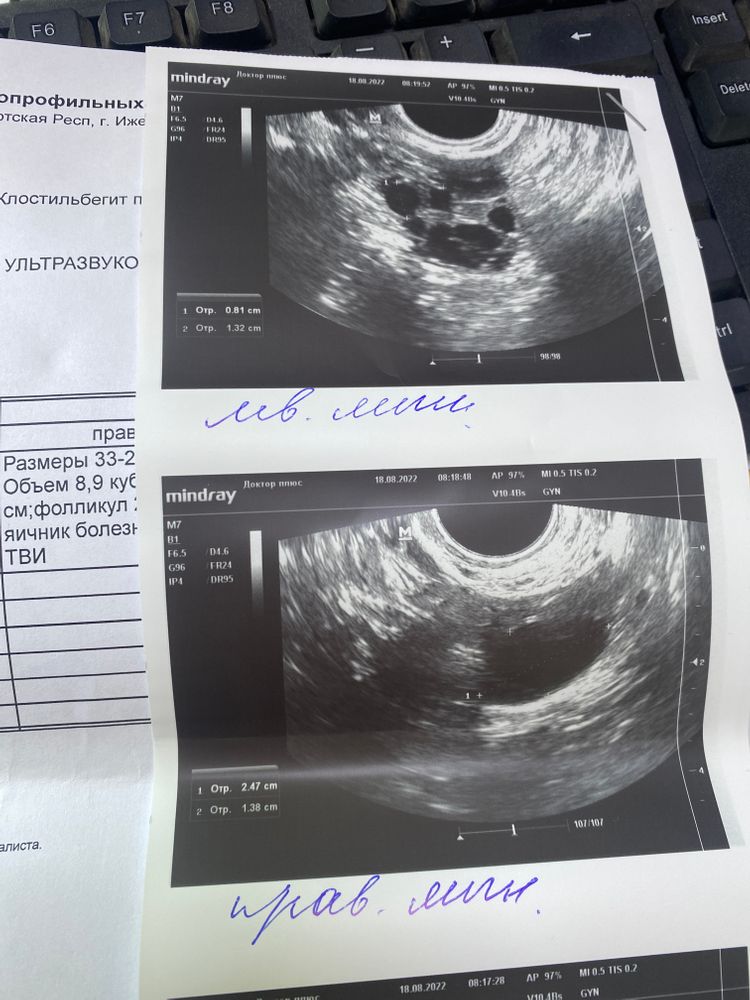

Здравствуйте, планируем беременность с 26.10.2022, в этом цикле проводили стимуляцию овуляции, с 5 до 9 ДЦ пила по одной таблетке клостилбегита. Сегодня 12 ДЦ, вчера была на фолликулометрии. Кстати в 2018 году у меня была операция (разрыв кисты на правом яичнике), то есть он остался меньше левого. Так вот вчера на фолликулометрии правый яичник был увеличен и ДФ был в нем, размером 25*14мм, врач сказала если есть то надо сделать укол овитрель, вчера его не нашла, можно ли его не ставить? Фолликул после стимуляции может сам лопнуть? Кстати яичник при ТВИ был болезненным